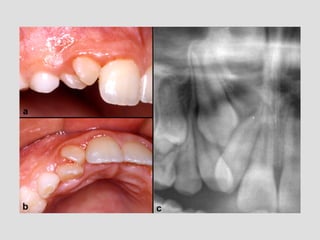

Dental anomalies in Cleft lip and palate patients

• The incidence of dental anomalies is

54%(15% normal population)

• Missing teeth

• Supernumerary

• Enamel hypoplasia

• Morphology anomalies

• Impacted teeth (1

• Missing upper lateral incisor (30-50%)

⬥In deciduous dentition some teeth could be smaller in

the cleft side

⬥Males- laterale incisor and second molar

⬥Females - central and lateral incisors

!

⬥In permanent dentition always lateral incisor

congenitally missing